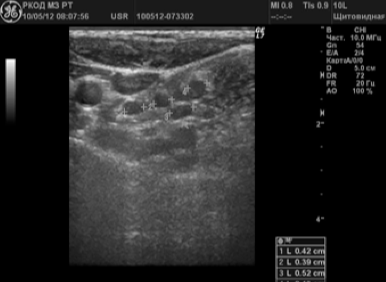

În 58 (38,2%) cazuri a fost suspectat ganglionilor limfatici metastatic. Alterarea LT avea dimensiuni de 6 până la 65 mm; 72,4% din nodulii limfatici au avut o formă sferică, P / PP<2,0; 10,3% — овальную, П/ПЗ>2,0; 17,3% - o formă neregulată sub formă de conglomerate. În 24 (41,4%) pacienți au fost identificați un singur ganglionilor limfatici schimbare; 34 (58,6%) - multiple. In 79,3% din ganglionii limfatici a fost nici o diferențiere în cortexul și poarta; 20,7% - poarta de acces determinat ca un mic incluziuni hiperecogene. 70,8% au fost ganglionii limfatici gipoehogennymi (Figura 3). 12% - anehogennoe; 17,2% - structura neomogena cu porțiuni ridicate și ecogenicitate coborâte clorhidric cu incluziuni lichide și calcifieri (Figura 4.).

Neck metastaze nodul limfatic in cancerul tiroidian